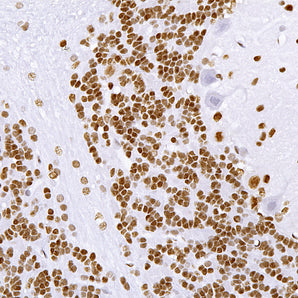

Cell Type Marker